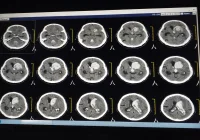

Photon-counting detector CT (PCD-CT) is a cutting-edge advancement in CT imaging technology that addresses limitations of conventional methods. It enhances visualisation of small anatomical structures and may enable higher precision with lower radiation exposure. The unique features of PCD-CT require updated scanning protocols for various diagnostic tasks. Early studies in paediatric populations show promising results in lung, abdomen, and bone imaging, but research on cardiac and vascular imaging is limited. A recent review published in Radiology Advances provides an overview of PCD-CT principles, technical considerations, and its potential benefits in paediatric lung, cardiac, and vascular imaging.

Current energy-integrating detector CT (EID-CT) relies on solid-state scintillator crystals to convert x-ray photons into visible light, which is then transformed into an electrical signal. However, this process has limitations, including reduced spatial resolution due to septa between detector elements, underweighting of lower energy photons affecting image contrast, increased electronic noise at lower doses, and limitations in dual-energy CT (DECT) imaging. In contrast, photon-counting detector CT (PCD-CT) directly converts x-ray photons into electrical signals using semiconductor materials. PCD-CT offers advantages such as smaller detector elements, higher spatial resolution, improved iodine contrast-to-noise ratio, reduced electronic noise, and enhanced spectral imaging capabilities. These technical advancements make PCD-CT a promising option for various diagnostic tasks.

Photon-counting detector CT (PCD-CT) offers significant clinical benefits in thoracic imaging, particularly in evaluating parenchymal lung disease, lung nodules, and mediastinal masses. For parenchymal lung disease, PCD-CT provides improved visualization of fine structures in the lung parenchyma compared to conventional CT (EID-CT), due to thinner slices and larger matrix sizes. Studies demonstrate enhanced detection of bronchial walls and pathologies such as honeycombing, fibrosis, and emphysema with PCD-CT. Additionally, PCD-CT enables greater dose reductions while maintaining diagnostic image quality compared to EID-CT. In lung nodule characterization, PCD-CT's thinner slices and larger matrix sizes enhance edge definition and shape characterization, potentially impacting management decisions such as metastasectomy. In evaluating mediastinal masses, PCD-CT achieves significant dose reductions while maintaining diagnostic image quality compared to EID-CT. Studies show a reduction in radiation dose by up to 65% with PCD-CT, making it a favourable option for pediatric patients. Overall, PCD-CT improves diagnostic accuracy, enhances image quality, and reduces radiation dose in thoracic imaging, making it a valuable tool in clinical practice.

In cardiovascular imaging, photon-counting detector CT (PCD-CT) offers notable advantages in evaluating congenital heart lesions, extracardiac vessel anomalies, and stents. For congenital heart disease assessment, PCD-CT provides higher contrast-to-noise ratios compared to conventional CT (EID-CT) with equivalent radiation doses. It enhances visualisation of normal anatomic structures and intracardiac pathology, potentially eliminating the need for further dedicated coronary artery imaging. PCD-CT's higher resolution enables better definition of coronary artery origins and proximal branches. In stent evaluation, PCD-CT overcomes artifacts associated with conventional CT, allowing for more accurate measurement of stent diameters and luminal patency. This capability is particularly valuable for children with obstructive lesions or ductus-dependent circulation. In thoracic vessel assessment, PCD-CT's higher spatial resolution and iodine signal improve characterization of vascular pathologies such as aortic coarctation, patent ductus arteriosus, and pulmonary embolism. It offers better edge and size definition compared to EID-CT, with the potential for dose reduction. Overall, PCD-CT enhances diagnostic accuracy and reduces radiation dose in cardiovascular imaging, making it a valuable tool for paediatric patients with congenital heart disease and vascular anomalies.